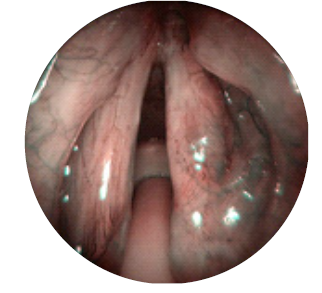

Ao exame objetivo apresentava papilomas na laringe: comissura anterior, terço posterior da corda vocal esquerda e a meio do ventrículo direito. A pontuação total no sistema de estadiamento de Derkay foi de 5 (4+1). O grau de severidade e tipo de disfonia correspondeu a G1R1B0A0S1.

O doente teve alta no dia seguinte a cada procedimento. Foi medicado para o domicílio com esomeprazol 20 mg id antes do pequeno-almoço durante dois meses, antibioterapia com amoxicilina e ácido clavulânico 875 + 125 mg comprimidos 12/12h durante oito dias e analgésicos. Realizou consultas de seguimento na primeira semana e no primeiro mês após o final do ciclo de tratamentos. Na última consulta, no 3º mês após o ciclo de tratamentos, encontrava-se assintomático e ao exame objetivo não foram detetados papilomas. O epitélio das pregas vocais apresentava-se íntegro e normotrófico (fig. 3 e 4).